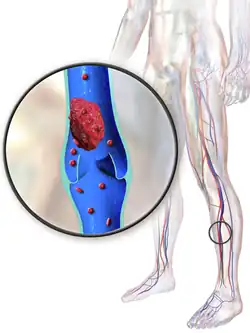

| Deep vein thrombosis; one of the prevalent symptoms of the syndrome | |

The signs and symptoms of the disease are mostly associated by the diagnostic feature of the disease, the presence of both pulmonary artery aneurysms and deep vein thromboses. Other symptoms to this disease are typically secondary to these two conditions, the common reported clinical symptoms present in patients are listed below;

- Peripheral venous thrombosis[3]